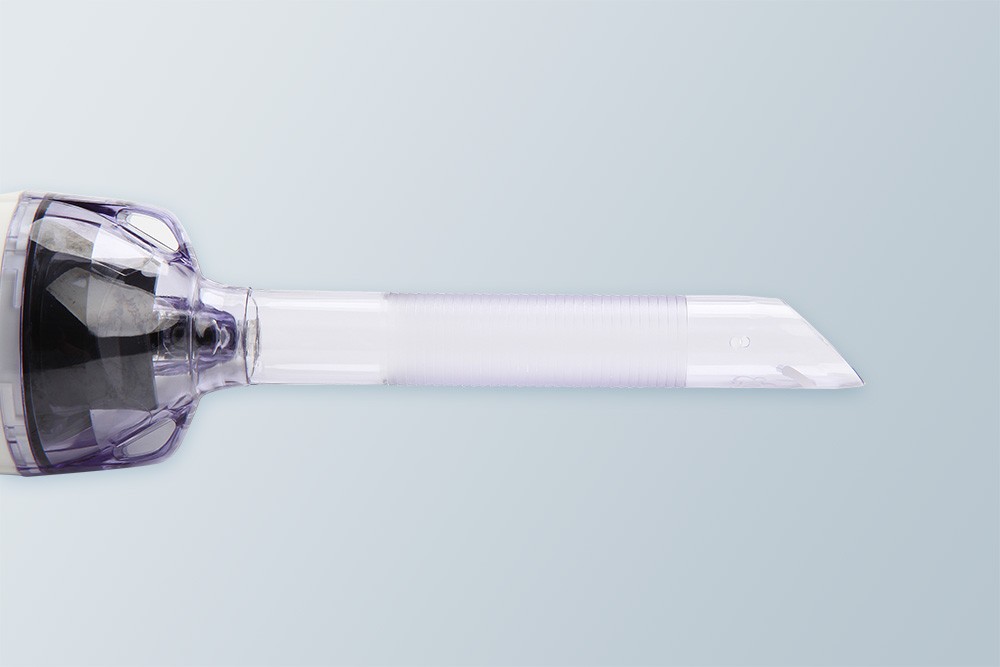

穿刺器有穿刺鞘管和穿刺芯两部分组成,穿刺芯主要任务就是和穿刺器鞘管一起,穿透腹壁全程,把穿刺鞘管留在腹壁上。穿刺鞘管主要任务就是让各种手术器械通过进入腹腔,医生可以进行手术操作,完成手术任务。

穿刺芯透明锥形头端 内镜直视下控制腹壁穿刺整个过程

不易损伤腹腔组织

不易损伤腹腔组织

鞘管头端45度斜面开口 标本容易进入鞘管,

给器械操作留出空间

给器械操作留出空间